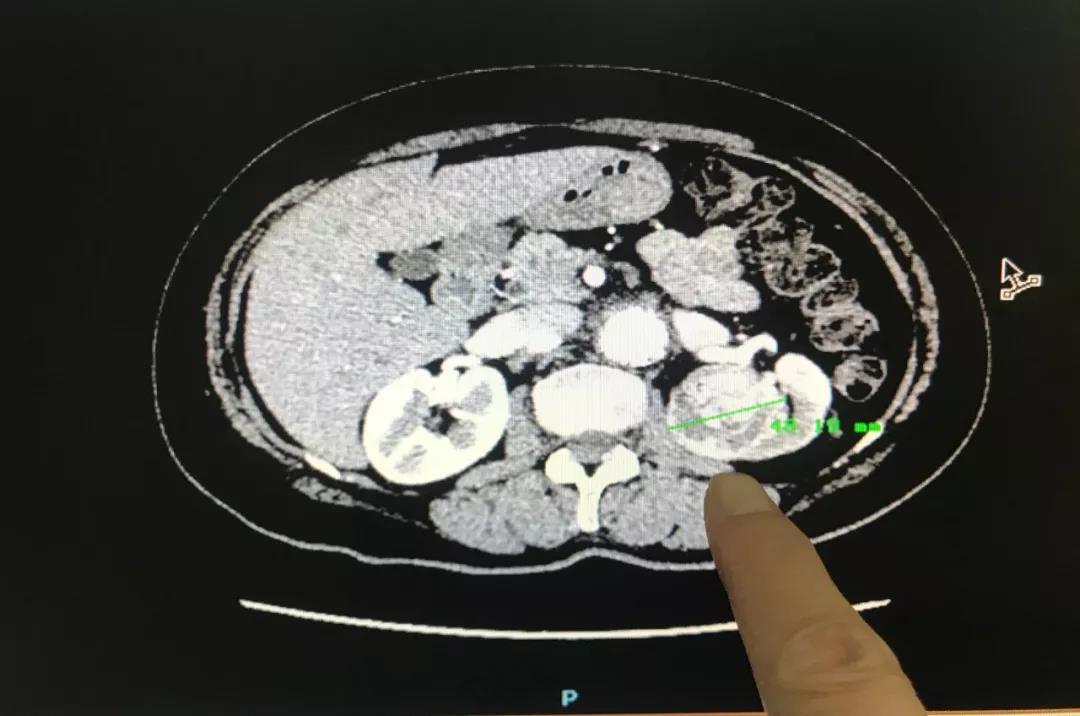

林英立博士接診後(hòu)詳細詢問了王阿姨之前的病史,随即安排了相關檢查。“從B超檢查結果可以發(fā)現腎占位腫瘤已經(jīng)增長(cháng)至4.8公分,比原來增大了很多,這(zhè)并不是一個好(hǎo)的征兆。”